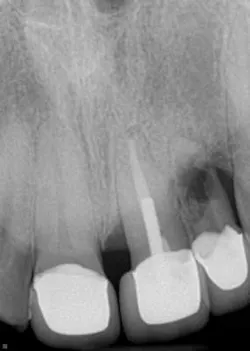

Internal root resorption is typically detected clinically via routine radiographs. It is observed in all areas of the root canal, but it is most commonly discovered in the cervical region of the tooth. (3) One of the key ways to diagnose internal resorption (vs. external resorption) is to observe whether or not there is a defined outline of the pulp chamber. If the pulp chamber outline is within the lesion itself, it is likely internal resorption. If the pulp chamber outline is recognizable within a radiolucent halo, then it is likely external resorption. The use of CBCT has allowed for more accurate and complete diagnosis of IRR (and external root resorption) and is highly recommended in early presentations of potential resorption. (2,3)

A healthy 36-year-old male presents to the office with a chief complaint of a loose front tooth. A radiograph revealed significant bone loss around tooth No. 10 in addition to the focalized loss of internal tooth structure in the apical one-third of the root. Obvious perforation of the root was observed. Clinical exam revealed a lack of recession, probing depths of 8+ mm with a Class III mobility. No drainage point or fistula were noted. The patient indicated that he had the crowns placed in the anterior area eight years ago and has not had any complications since then. He furthermore admits to lack frequent dental visits during this time.

Differential diagnoses of internal and external resorption were given. Earlier radiographs would definitely aid in a more accurate and definitive diagnosis, but ultimately, internal resorption was given due to the focal point of radiolucency within the pulp chamber area. While there could be debate on this, the ultimate fate of the tooth did not change. Due to the extent of the defect (perforation through external root surface) and the advanced bone loss and periodontal disease, it was recommended that that tooth be removed and other restorative options be assessed. Upon removal of the tooth, there was very little root structure left as it came out in a multitude of pieces.